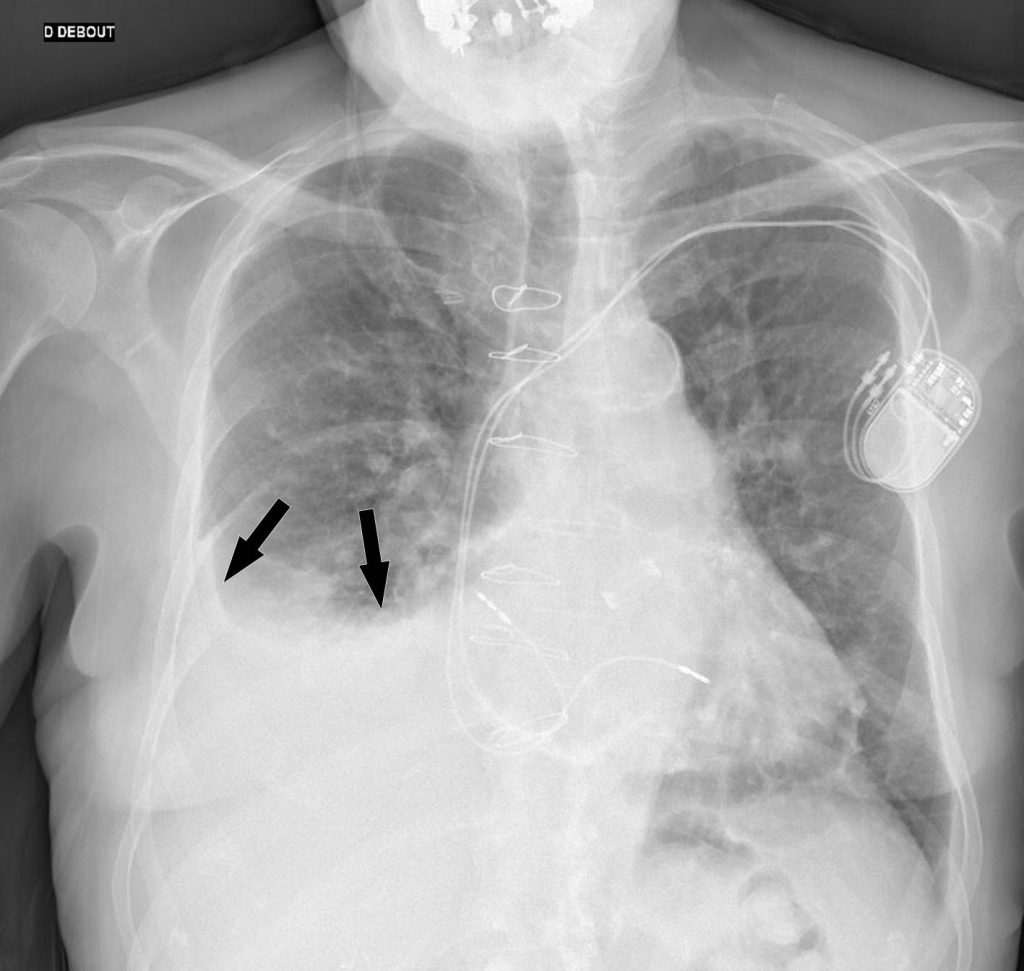

Fig. 91.1. Radiographie de face debout d’un épanchement pleural droit libre de moyenne abondance.

Opacité hydrique déclive de la base de l’hémithorax droit, effaçant le diaphragme et le bord droit du cœur, à limite concave vers le haut et vers l’intérieur (flèches).

Source : CERF, CNEBMN, 2022.

Fig. 91.2. Radiographie de face debout et scanner non injecté d’un épanchement pleural gauche de grande abondance.

L’opacité hydrique déclive de la base de l’hémithorax gauche, efface le diaphragme et le bord gauche du cœur. Elle présente une limite supérieure concave vers le haut et vers l’intérieur, réalisant une ligne de Damoiseau (flèches en A). Le scanner chez le même patient montre l’épanchement de grande abondance (astérisque en B) déclive avec une limite concave vers le haut et vers l’intérieur (flèches).